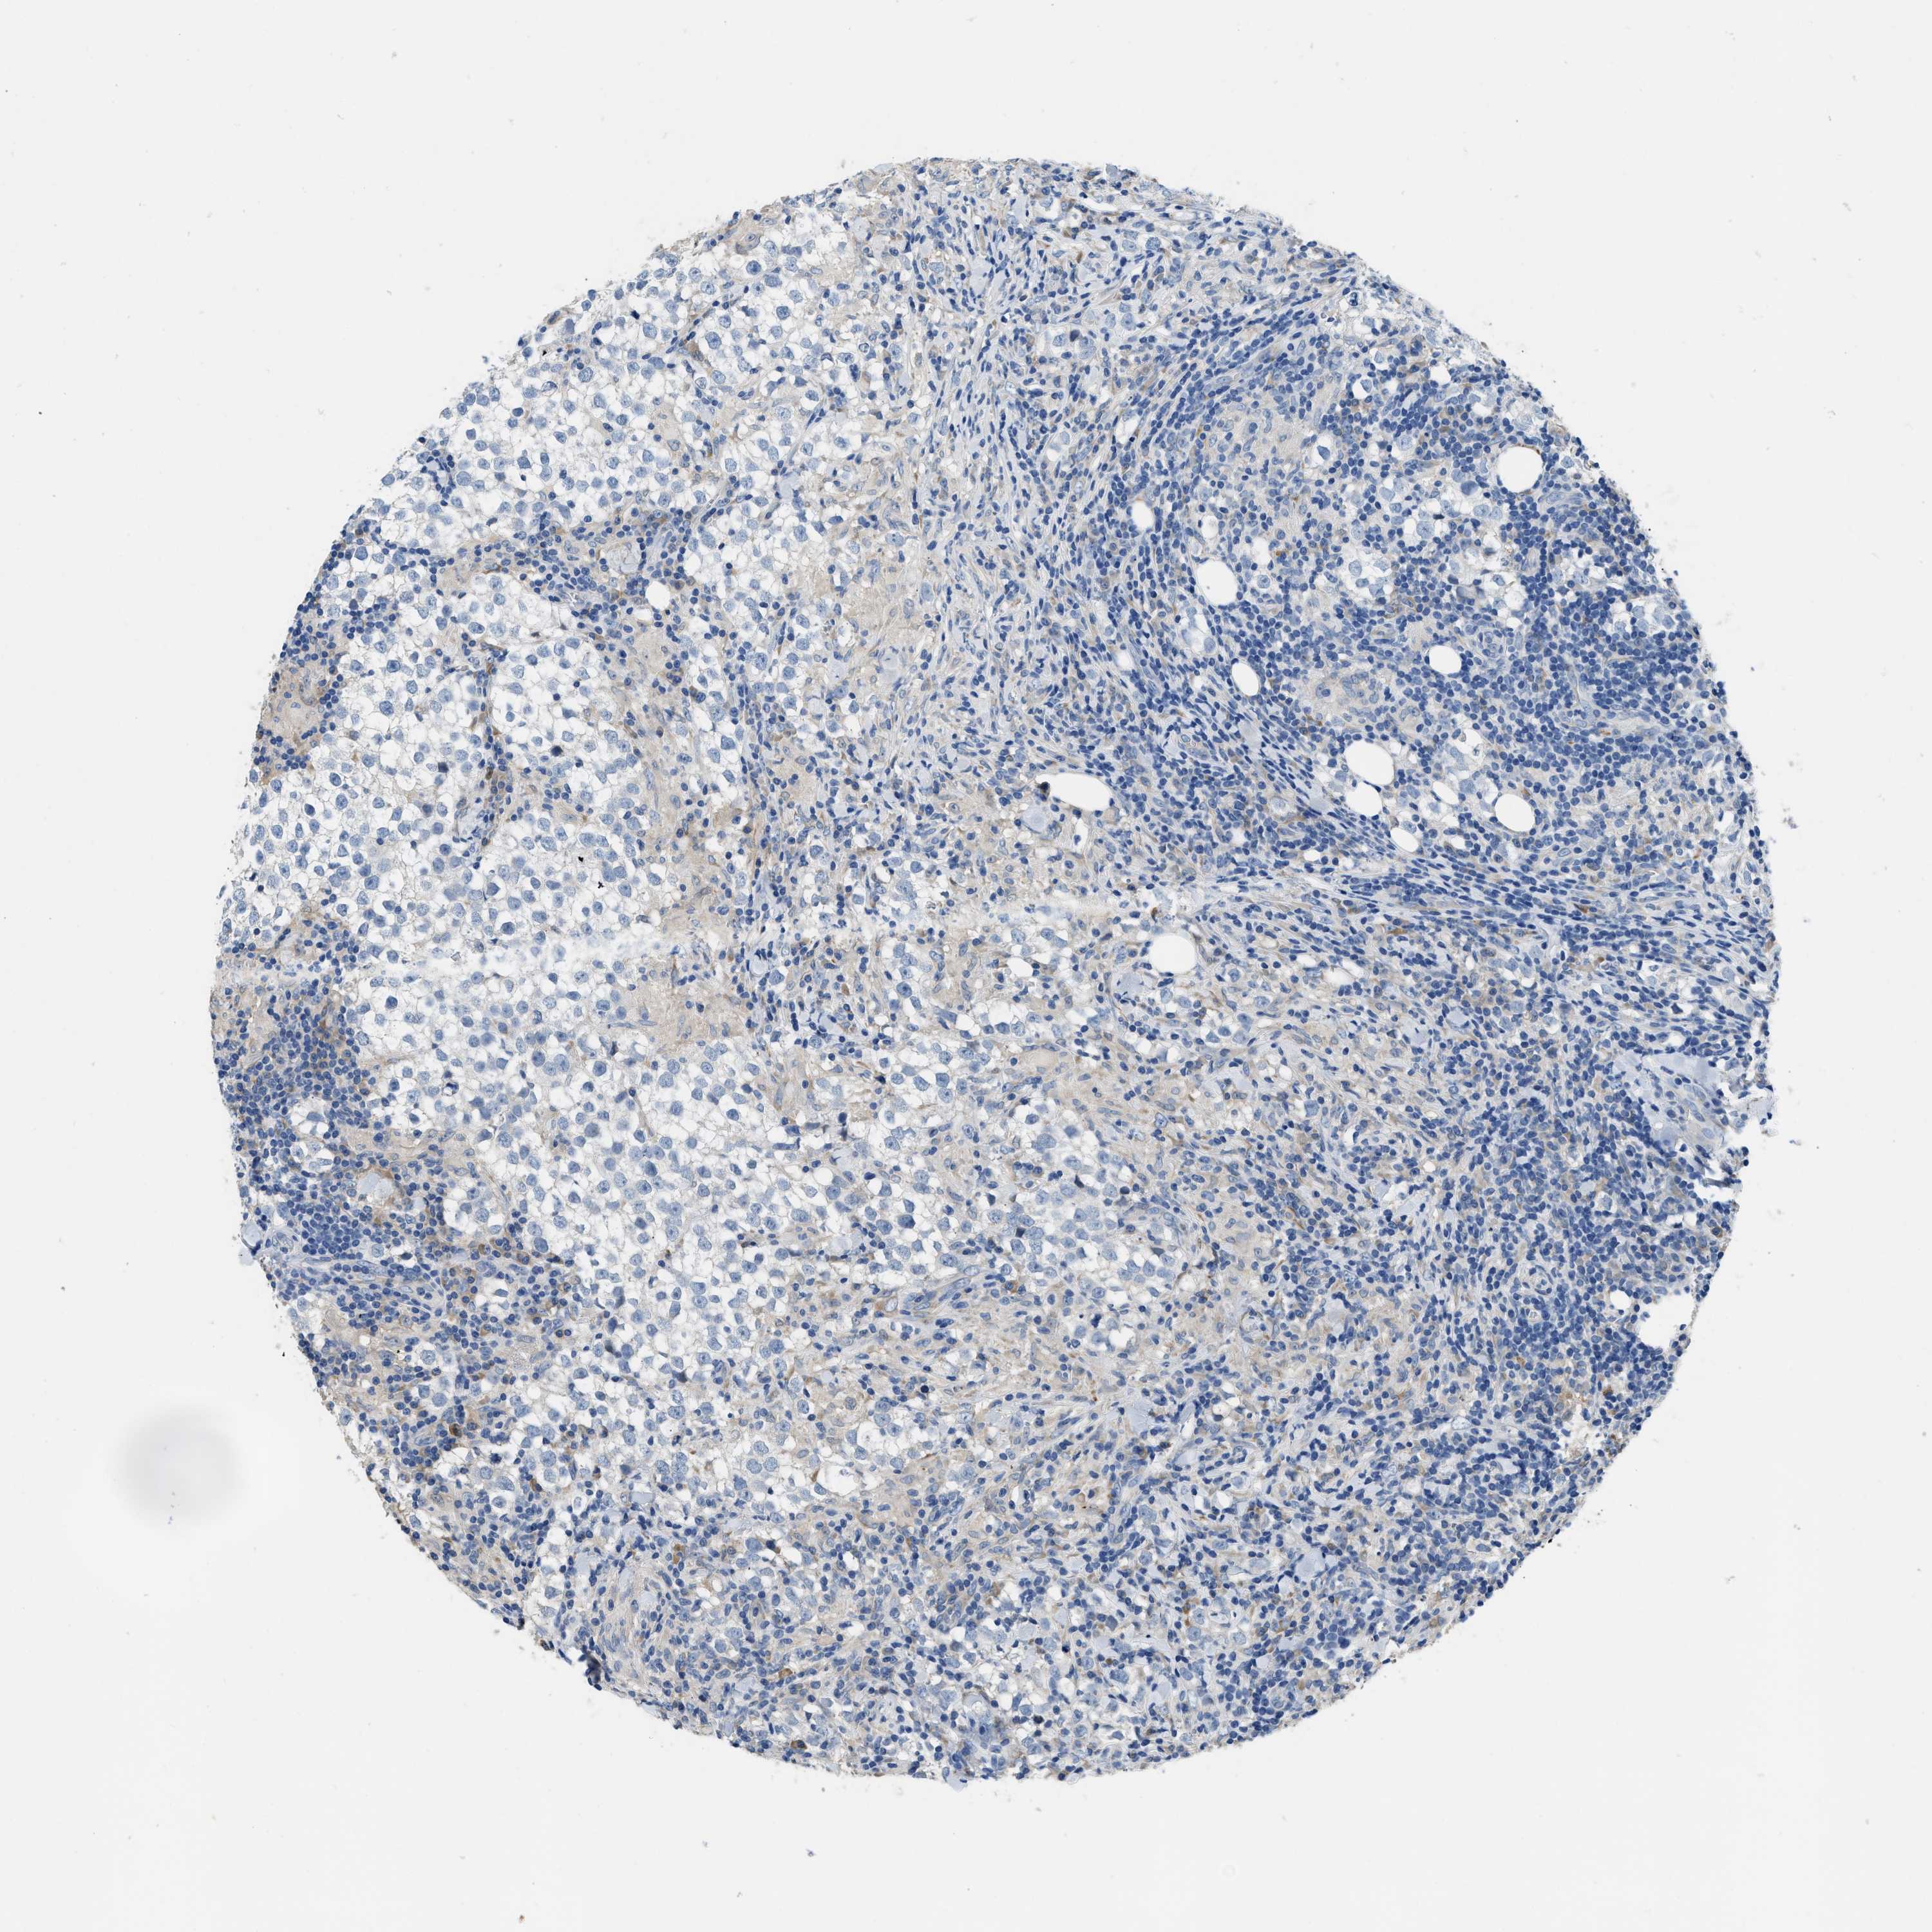

TESTIS CANCER - Protein expressioni

A mouse-over function shows sample information and annotation data. Click on an image to view it in a full screen mode. Samples can be filtered based on level of antibody staining by selecting one or several of the following categories: high, medium, low and not detected. The assay and annotation is described here.

Note that samples used for immunohistochemistry by the Human Protein Atlas do not correspond to samples in the TCGA dataset.

Antibody stainingi

Antibody staining in the annotated cell types in the current human tissue is reported as not detected, low, medium, or high, based on conventional immunohistochemistry profiling in selected tissues. This score is based on the combination of the staining intensity and fraction of stained cells.

Each image is clickable and will lead to virtual microscopy that enables deeper exploration of all samples and also displays staining intensity scores, fraction scores and subcellular localization as well as patient and tissue information for each sample.

Antibody HPA018852

Antibody CAB016722

Staining

High

Medium

Low

Not detected

Intensity

Strong

Moderate

Weak

Negative

Quantity

>75%

75%-25%

<25%

None

Location

Nuclear

Cytoplasmic/membranous

Cytoplasmic/membranous,nuclear

Carcinoma, Embryonal, NOS

Seminoma, NOS